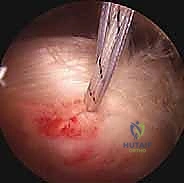

في هذا الدليل الطبي المرجعي والشامل، سنتعمق بشكل غير مسبوق في فهم اعتلال والتهاب وتر العضلة ذات الرأسين. سنبدأ بتشريحه المعقد الذي يجعله عرضة للإصابة، مروراً بالمسببات البيوميكانيكية، وعوامل الخطر، والأعراض السريرية المميزة. وصولاً إلى استعراض شامل لأحدث خيارات التشخيص والعلاج المتاحة عالمياً. وسنركز بشكل مكثف على تقنيات "العلاج بالمنظار الجراحي"، والذي يمثل الثورة الأهم في جراحة الكتف الحديثة، موفراً حلولاً جذرية وفعالة بحد أدنى من التدخل الجراحي.

بصفتنا خبراء رواد في جراحة العظام، المفاصل، والطب الرياضي، فإننا نؤمن إيماناً راسخاً بأهمية التثقيف الطبي وتزويد المرضى بالمعلومات الدقيقة، الموثوقة، والشاملة لتمكينهم من اتخاذ قرارات مستنيرة وواثقة بشأن صحتهم. وفي هذا السياق الطبي المتقدم، يبرز اسم الأستاذ الدكتور محمد هطيف في العاصمة صنعاء كمرجع علمي وطبي رائد في تشخيص وعلاج حالات الكتف الأكثر تعقيداً. بخبرة تتجاوز العشرين عاماً، ومكانة أكاديمية رفيعة كأستاذ في جامعة صنعاء، يسخر الدكتور هطيف أحدث التقنيات الجراحية بالمنظار لضمان استعادة المرضى لوظائفهم الحركية بأعلى درجات الأمان والنجاح.